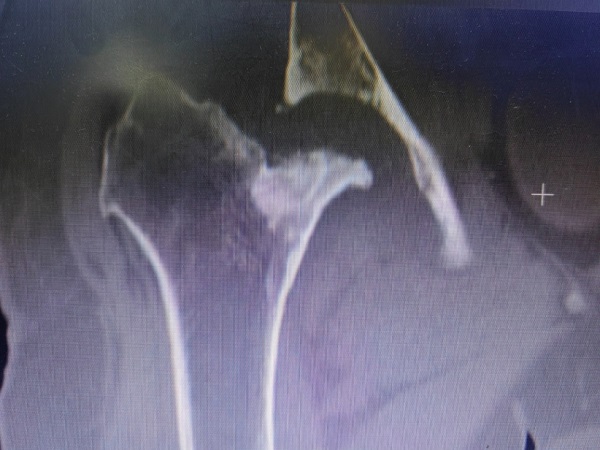

李師傅病程長,情況復雜,檢查發(fā)現(xiàn)其骨盆傾斜,股骨頭、頸部分缺如,髖臼嚴重骨缺損,髖關節(jié)半脫位,患肢短縮近6cm,髖關節(jié)周圍軟組織攣縮。手術難度大,髖部股神經、坐骨神經以及股動脈牽張損傷的風險很大,創(chuàng)傷骨科郭永良主任和王爭剛主任醫(yī)師經過充分術前討論,制定出了細密的個性化手術方案,并與患者及家屬充分交流和溝通。